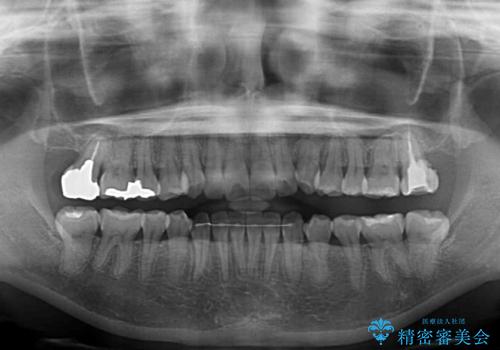

IPR(歯と歯の間を削る処置)によりスペースを獲得して上下顎前歯のデコボコを改善し、前歯が前方に突出しないように設定した上で、インビザラインにて矯正治療を行うこととしました。

途中体調を崩され、長い期間矯正治療を休むことになったため4年半ほどの治療期間がかかりました。